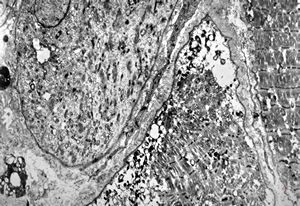

F,32y. | transversally sectioned skeletal muscle cell

mouse skeletal muscle cell - transversal section